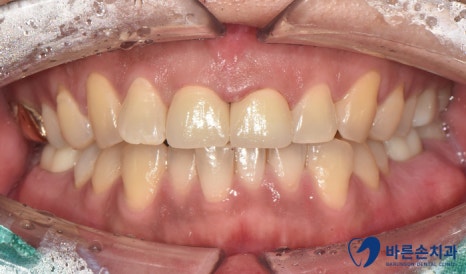

저희 병원에 내원 해 주신 환자분의 사진을 보며 설명해 드리도록 하겠습니다^^

환자분의 경우 육안상으로 보아도 치아의 손상도가 커 보이는데요

치료 전 후를 비교해 볼까요?

치료전 치료후

자연스럽게 크라운이 완성되었네요.